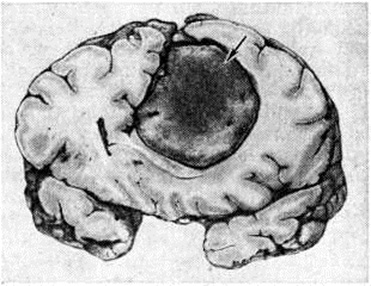

МенингиомаМенингиома (meningioma, греческий meninx, meningos мозговая оболочка + -oma; синонимы: грибовидная опухоль твёрдой мозговой оболочки, фиброэндотелиома, менинготелиома, арахноидэндотелиома, арахноидальная менингиома, менингеальная фибробластома, менингобластома) — внемозговая, в большинстве случаев доброкачественная опухоль, исходящая из твёрдой, реже мягкой оболочки головного или спинного мозга, редко из сосудистого сплетения мозговых желудочков или возникающая эктопически в костях черепа, позвоночника и по ходу нервных корешков. По локализации различают: 1. Менингиома оболочек головного мозга: 1) конвекситальную; 2) парасагиттальную — встречается вдоль угла, образованного стенкой верхнего продольного синуса и твёрдой мозговой оболочкой выпуклой поверхности больших полушарий; может сдавливать синус или врастать в него; 3) большого серповидного отростка; 4) тенториальную; 5) твёрдой мозговой оболочки основания мозга: а) передней черепной ямки — ольфакторной ямки, бугорка турецкого седла; б) средней черепной ямки — крыльев основной кости; в) задней черепной ямки — блюменбахова ската, края большого затылочного отверстия. 2. Менингиома оболочек спинного мозга. 3. Внутрижелудочковую Менингиома, исходящую из сосудистого сплетения. 4. Экстрадуральную Менингиома — исходит из наружных слоёв твёрдой мозговой оболочки, часто инфильтрирует прилежащие кости черепа, стенки позвоночного канала. Менингиома, связанные с оболочками зрительного нерва, располагаются в зрительном канале, в полости орбиты. 5. Эктопическую Менингиома—встречается в костях черепа и позвоночника, в придаточных полостях носа, в полостях внутреннего и среднего уха, по ходу нервных корешков. Микроскопически Менингиома обычно представляет собой хорошо отграниченный узел округлой или полдовоидной формы (рисунок 1), нередко спаянный с внутренней поверхностью твёрдой мозговой оболочки. Встречаются и плоские узлы. Спинальная Менингиома чаще продолговатая, при экстрадуральном расположении может муфтой охватывать дуральный мешок. По величине Менингиома варьируют в диаметре от нескольких миллиметров до 15 сантиметров и более. Консистенция Менингиома довольно плотная, особенно при обилии фиброзной ткани. В большинстве случаев опухоль окружена плотной капсулой. На разрезе ткань Менингиома серо или мясо-красная, при обильном содержании так называемый ксантомных клеток принимает охряную окраску. Наличие кист в Менингиома не характерно. Менингиома обычно одиночны, но могут быть и множественные. В редких случаях множественная Менингиома сочетается с множественной невриномой — болезнь Реклингхаузена (смотри полный свод знаний Нейрофиброматоз). Гистологический классификации Менингиома не отличаются существенно одна от другой. Согласно гистологической классификации опухолей центральная нервная система, принятой Комиссией ВОЗ по опухолям мозга (Женева, 1976), выделяются следующие подтипы Менингиома: Менинготелиоматозная Менингиома (эндотелиоматозная, синцитиальная, арахноидэндотелиоматозная). Состоит из мозаикоподобно-расположенных мономорфных клеток с овальным или округлым ядром, содержащим умеренное количество нежных зёрен хроматина. Строма представлена немногочисленными сосудами и редкими тонкими тяжами соединительной ткани, окаймляющими клеточные поля. Характерны, но не всегда встречаются концентрические структуры, подобные разрезанной луковице, из наслаивающихся одна на другую уплощённых опухолевых клеток. Гиалинизированный центр такой структуры нередко обызвествляется (так называемый псаммомное тельце). Фиброзная Менингиома (Фибробластическая). Построена из фибробластоподобных клеток, которые располагаются параллельно друг другу и складываются в переплетающиеся между собой пучки, содержащие соединительнотканные волокна (рисунок 2). Ядра клеток вытянутые. Могут встретиться концентрические структуры, псаммомные тельца. Переходная Менингиома (смешанная). Включает структуры менинготелиоматозной и фиброзной Менингиома Псаммоматозная Менингиома — менинготелиоматозная или фиброзная Менингиома с большим количеством псаммомных телец. |

|  |